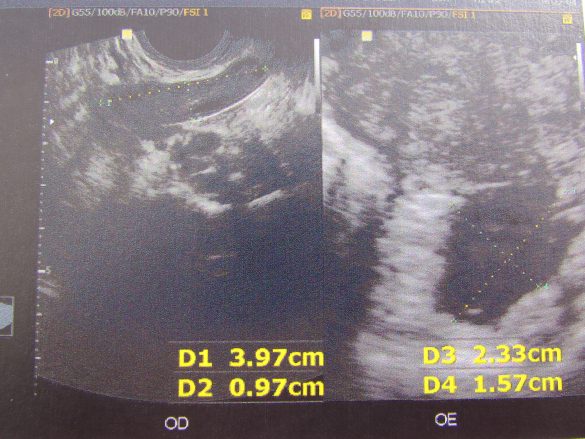

“A ultrassonografia transvaginal (USGTV) é um exame não invasivo, de baixo custo, boa tolerância à dor pelas gestantes e que permite ao médico avaliar com riqueza de detalhes o embrião, a vesícula vitelínica, se há gestação múltipla e determinar de forma mais assertiva a idade gestacional.

Estruturas com 1 mm são vistas com perfeição, por isso em casos de gestação inicial (menor que sete semanas) e sangramento vaginal no primeiro trimestre, é o exame mais indicado por permitir visualizar melhor pequenas alterações como os hematomas subcoriônicos (descolamento da placenta), ausência de batimentos cardio-embrionários, gestações ectópicas (nas trompas) ou até mesmo a ausência do embrião em gestações precoces com até dez semanas de evolução.

Por isso um conselho: é melhor que as mamães controlem a ansiedade e deixem para fazer a USGTV após a sétima semana de gestação. Nesta fase, a ultrassonografia será útil para a determinação da idade gestacional, detectar gestação múltipla e também para avaliação do útero e dos ovários.